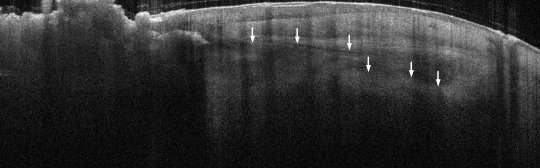

VA15: Right Dorsal Hand, Squamous Cell Carcinoma, Invasive, Keratoacanthoma type

- Arrows indicate extent of squamous mass